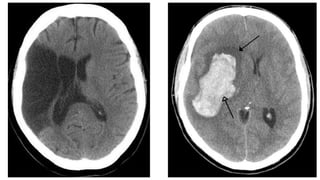

In patients with a clinical diagnosis of an acute

stroke, a CT scan that shows no intracerebral

haemorrhage makes an ischaemic stroke the

likelier diagnosis.

Keep In Mind Inpatients with a clinical diagnosis of an acute stroke, a CT scan that shows no intracerebral haemorrhage makes an ischaemic stroke the likelier diagnosis.